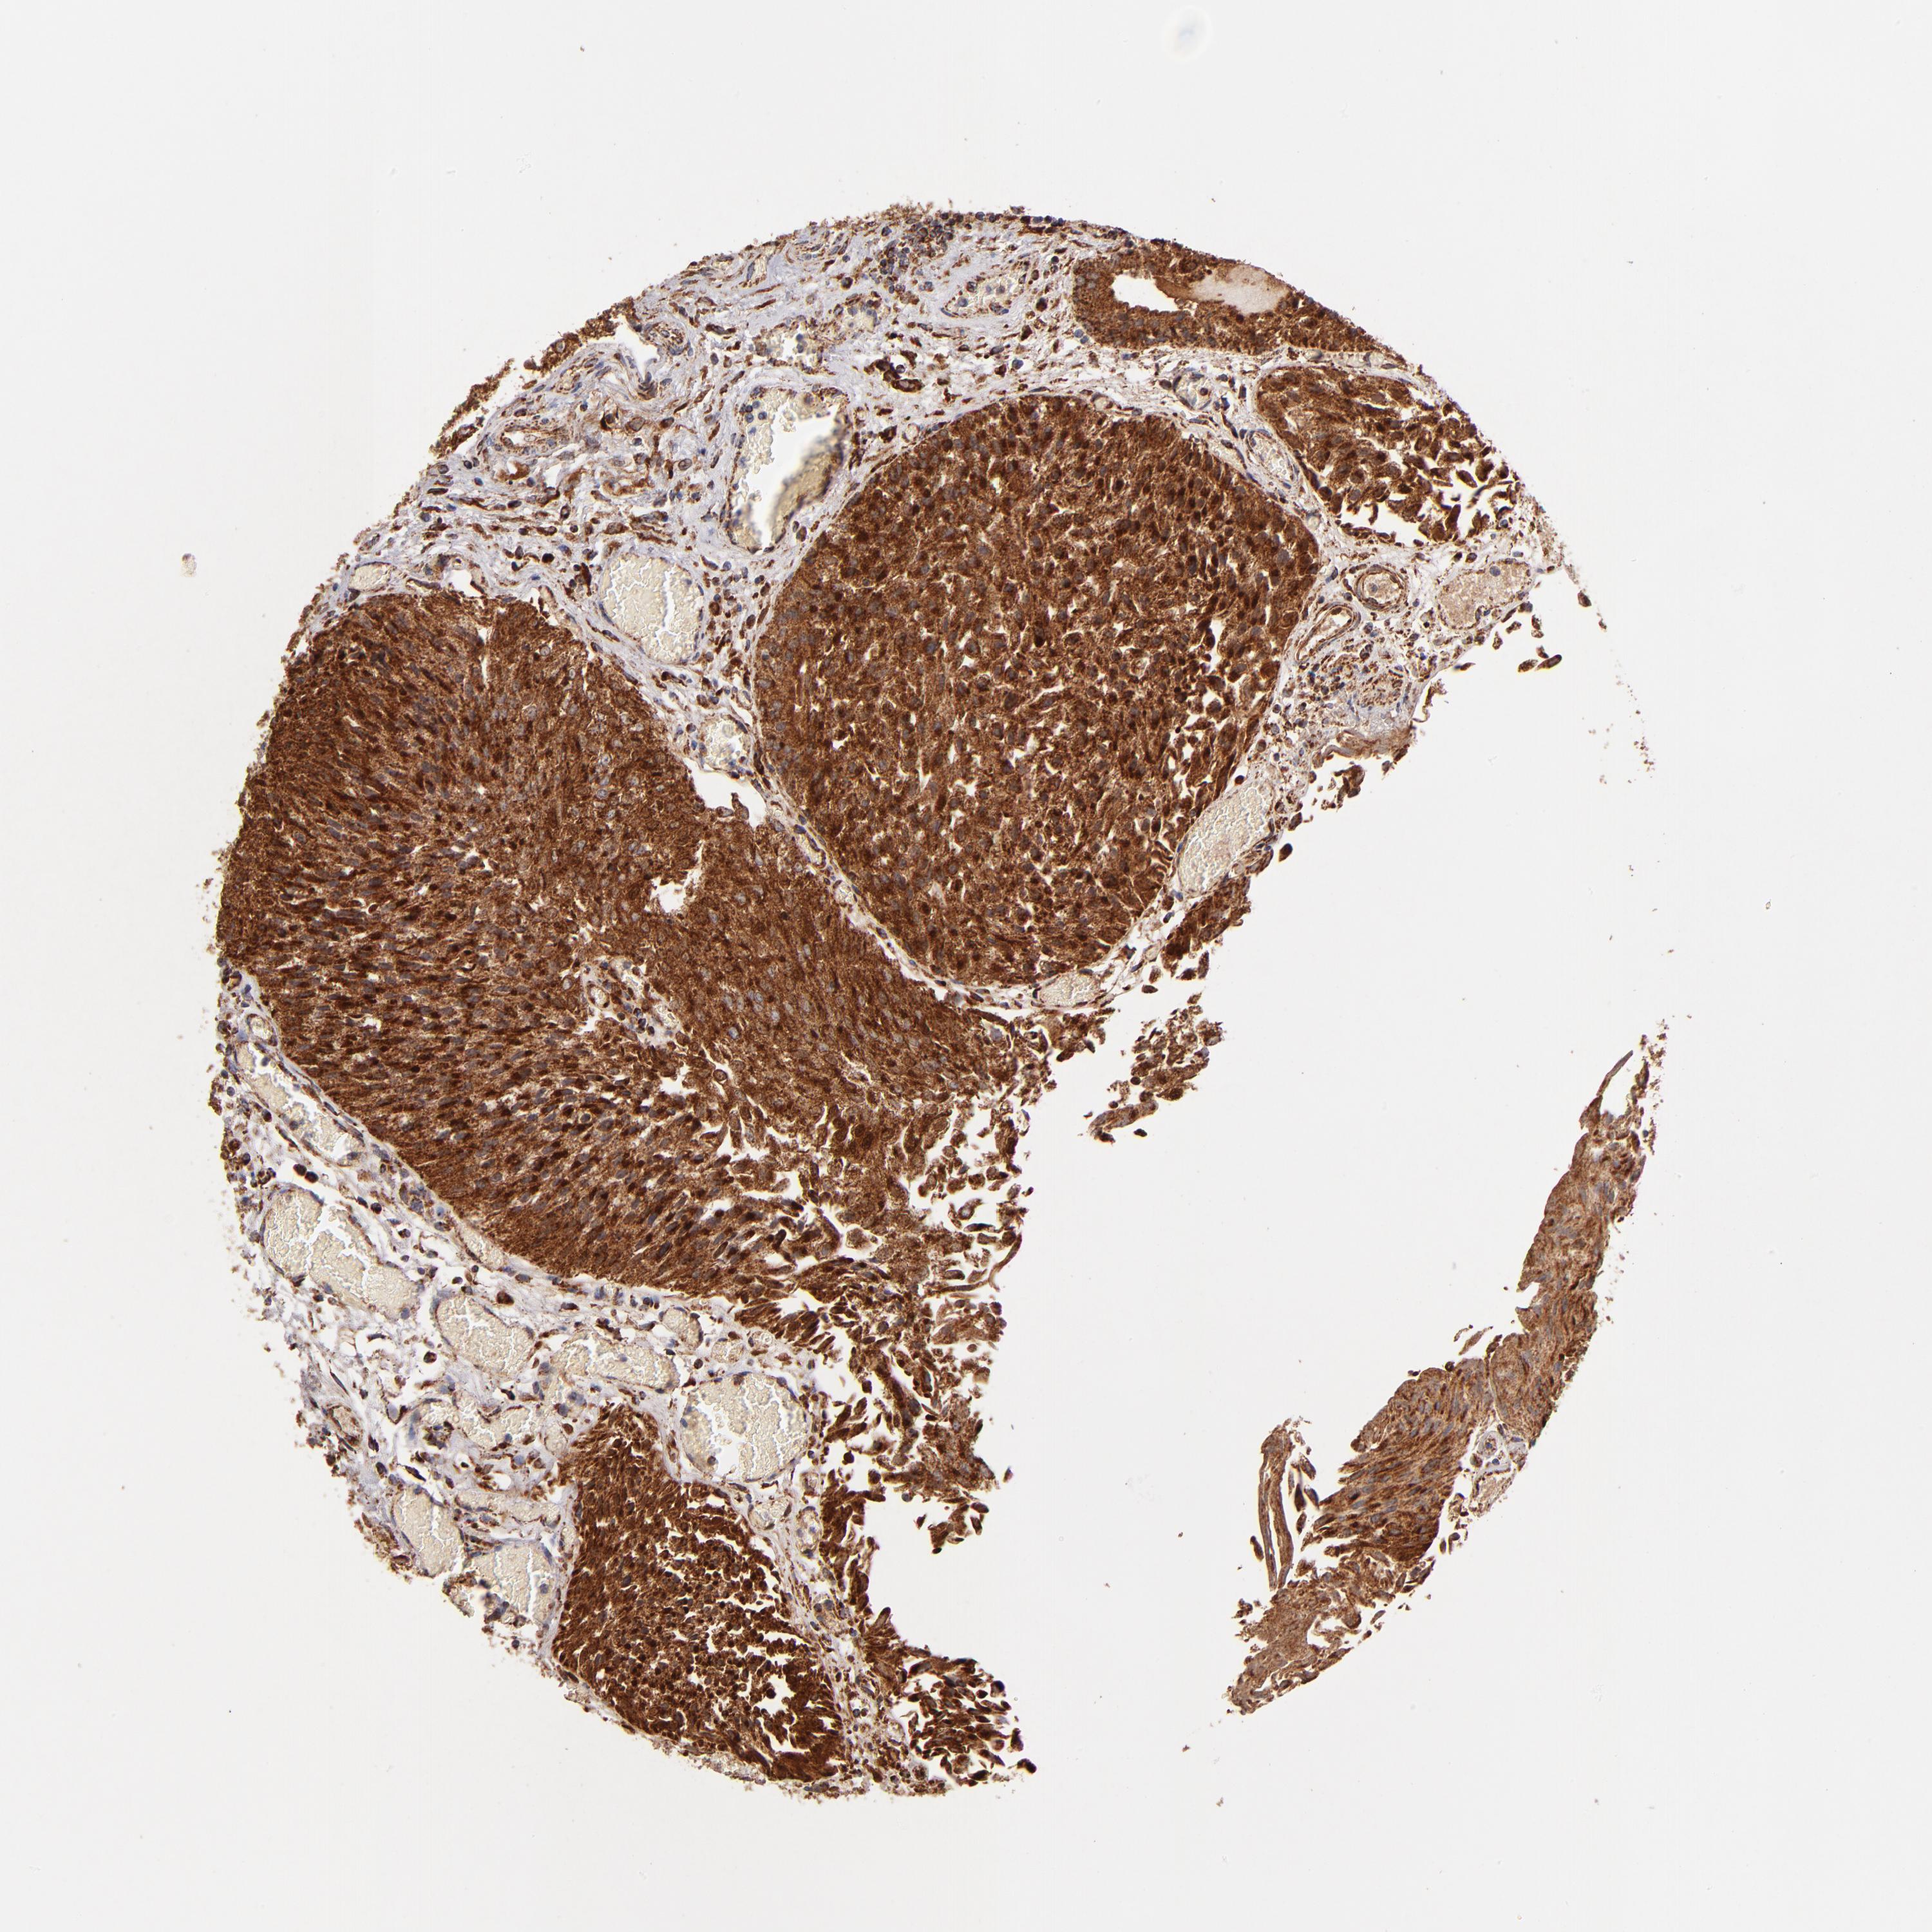

UROTHELIAL CANCER - Protein expressioni

A mouse-over function shows sample information and annotation data. Click on an image to view it in a full screen mode. Samples can be filtered based on level of antibody staining by selecting one or several of the following categories: high, medium, low and not detected. The assay and annotation is described here.

Note that samples used for immunohistochemistry by the Human Protein Atlas do not correspond to samples in the TCGA dataset.

Antibody stainingi

Antibody staining in the annotated cell types in the current human tissue is reported as not detected, low, medium, or high, based on conventional immunohistochemistry profiling in selected tissues. This score is based on the combination of the staining intensity and fraction of stained cells.

Each image is clickable and will lead to virtual microscopy that enables deeper exploration of all samples and also displays staining intensity scores, fraction scores and subcellular localization as well as patient and tissue information for each sample.

Antibody HPA003010

Staining

High

Medium

Low

Not detected

Intensity

Strong

Moderate

Weak

Negative

Quantity

>75%

75%-25%

<25%

None

Location

Nuclear

Cytoplasmic/membranous

Cytoplasmic/membranous,nuclear

Urothelial carcinoma, High grade

Urothelial carcinoma, Low grade